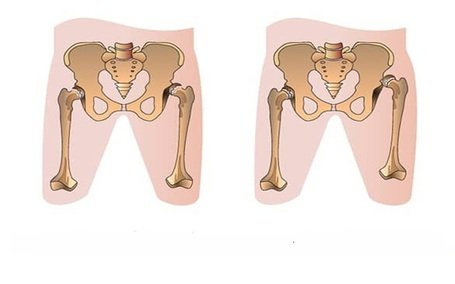

- Congenital Hip Dislocation – Pelvic osteotomies expert

Congenital Dislocation of Hip (CDH = DDH)

Read More -